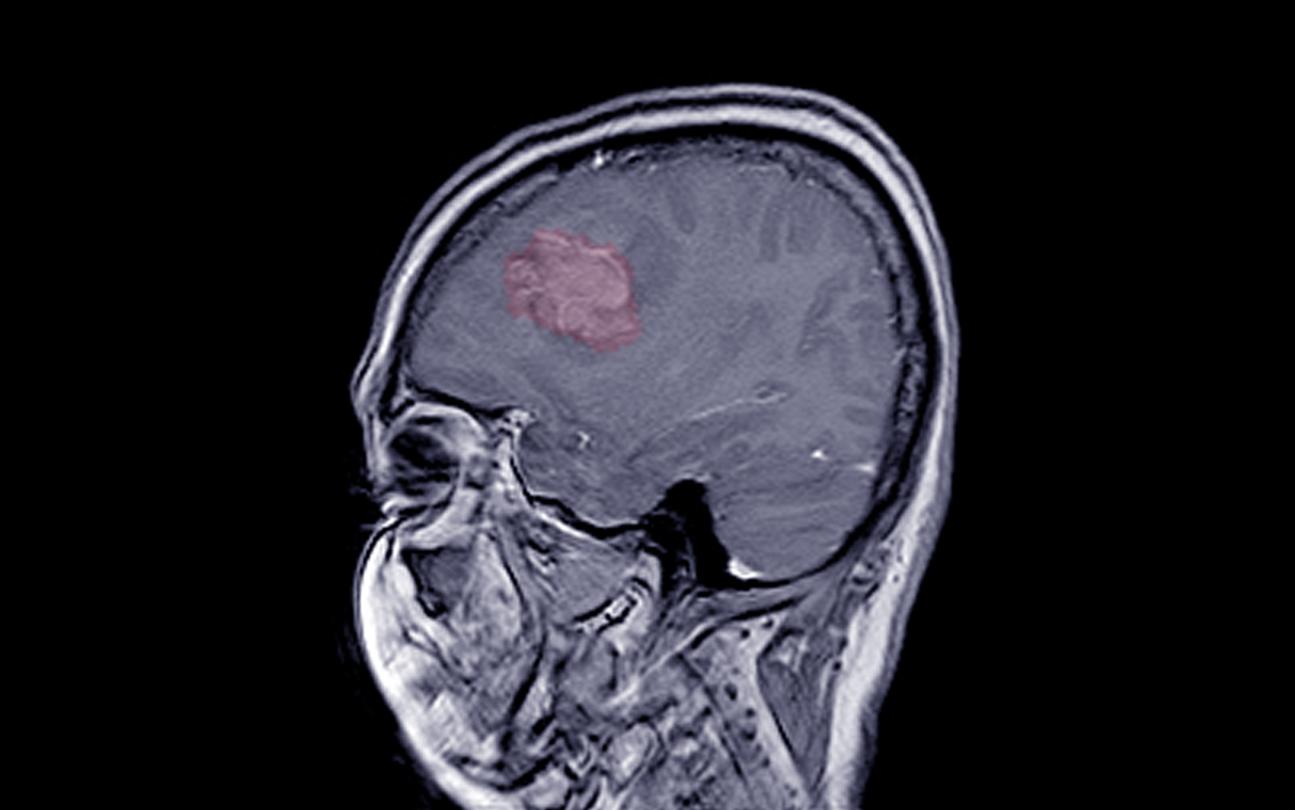

Alors que de précédents travaux avaient déjà mis en lumière un risque accru de tumeur au cerveau appelée méningiome après l’utilisation prolongée et à dose élevée des traitements progestatifs Androcur, Lutéran et Lutenyl, une étude du GIS Epi-Phare révèle un risque similaire avec 3 autres progestatifs : le Colprone, le Depo Provera et le Surgestone.

Les chercheurs français ont repris les dossiers de 18.061 femmes âgées de 45 à 74 ans (en moyenne 58 ans) et opérées d’un méningiome entre 2009 et 2018 en France ainsi que ceux de 90.305 femmes témoins. Les analyses ont révélé que l’utilisation prolongée (un an ou plus) de Colprone (traitement contre la préménopause, l'endométriose, les saignements ; substance active : medrogestone) est associée à un risque 3,5 fois plus élevé de méningiome. Les femmes qui ont pris sur une longue période le contraceptif injectable Depo Provera (acétate de médroxyprogestérone), ont 5,6 fois plus de risque de développer une tumeur au cerveau. Les patientes qui ont été exposées un an ou plus à la promégestone (Surgestone), avant la fin de sa commercialisation en 2020 en France, ont un risque multiplié par 2.

Pour l’équipe d’Epi-Phare, pas de doute : leur publication vient "à nouveau confirmer un effet des progestatifs sur le risque de méningiome intracrânien".